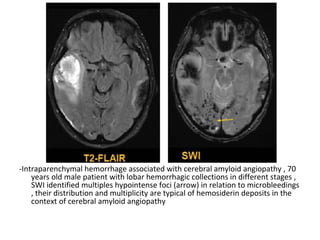

Enhancing infarcts , T1+C shows gyriform enhancement at the left insula and

posterior parietal lobe from a subacute left MCA infarct